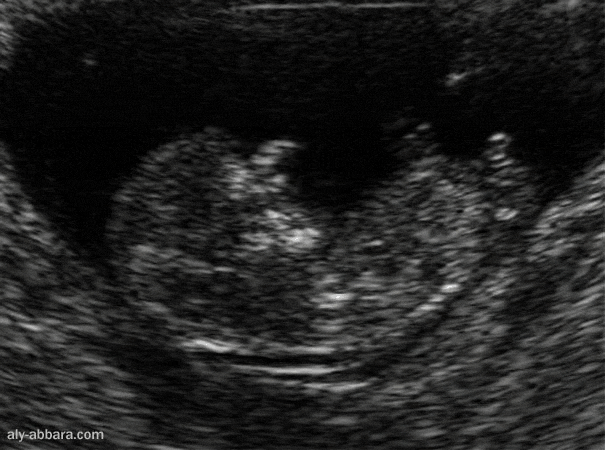

12 Semaine D Aménorrhée En Mois Foetus de 12 semaines d'aménorrhée ; clarté nucale